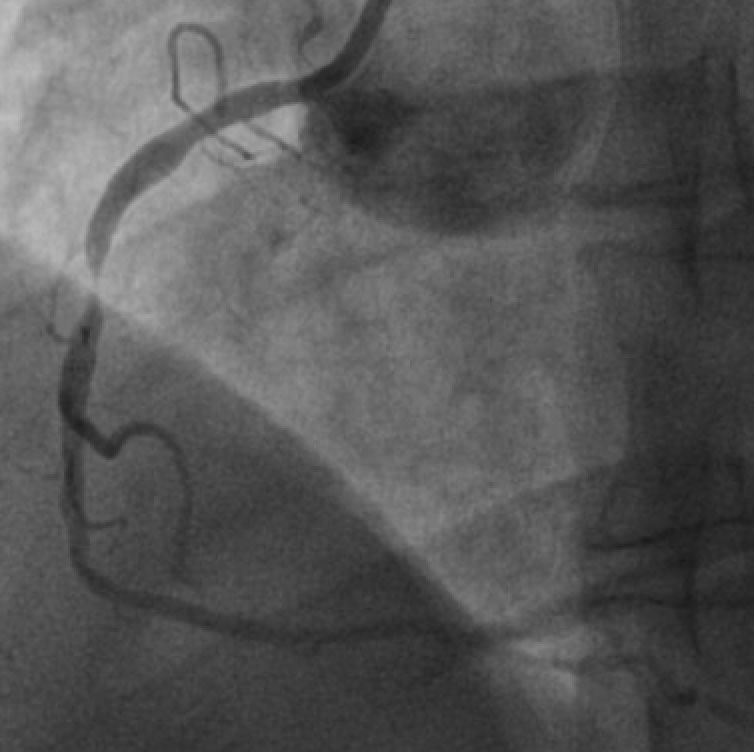

Before and After stenting example Cove Cardiology Dr Cuneyt Ada Jaw Pain After Stent Restenosis occurs when an artery that was opened with a stent or angioplasty becomes narrowed again. The gradual renarrowing of the area inside the stent, known as restenosis, and the formation of clots inside. Two main complications can occur with coronary stents: It can happen to men or women, but jaw pain linked to a. You can have episodes of. Jaw Pain After Stent.